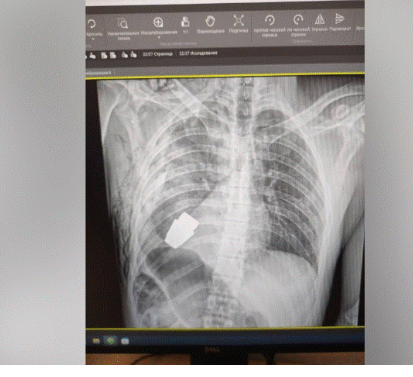

إزالة قنبلة غير منفجرة من صدر جندي أوكراني! - صورة

نجح فريق أطباء أوكراني في إزالة قنبلة يدوية غير منفجرة من صدر جندي، وفقا لما ذكرت شبكة "سي إن إن" الإخبارية.

وتضمنت الصور التي جرى نشرها على صفحة "المسعفون العسكريون الأوكرانيون" في موقع "فيسبوك" صورة بالأشعة السينية للجزء العلوي من جسد الجندي مع ظهور القنبلة اليدوية.

وكانت العملية الجراحية محفوفة بالمخاطر، إذ خشي الأطباء من أن تنفجر القنبلة اليدوية في أي وقت أثناء العملية، ولذلك أجريت الجراحة "بدون تخثير كهربائي"،  وهو علاج طبي يتحكم في النزيف باستخدام الكهرباء.

ووفقًا للمنشور، فقد أجريت العملية "بحضور اثنين من خبراء المتفجرات الذين كانوا يضمنون سلامة الطاقم الطبي".

وجاء في المنشور: "تم إجراء العملية بواسطة أحد أكثر الجراحين خبرة في القوات المسلحة الأوكرانية".

وأضاف أن الجراحة كانت ناجحة، لافتا إلى أن الجندي يقضي في الوقت الحالي فترة نقاهة "لمزيد من إعادة التأهيل والتعافي".

ووفقًا للمصدر، فإن المتفجرة التي كانت داخل جسد الجندي عبارة عن قنبلة "VOG"، وهي عبارة عن قنبلة بطول 4 سم تُطلق من قاذفة قنابل يدوية، ومصممة للانفجار فوق الأرض مباشرة، وقادرة على قطع مسافة 400 متر تقريبًا.

ولم تحدد صفحة "المسعفون العسكريون الأوكرانيون" زمان ومكان العملية الجراحية، أو كيفية إصابة الجندي.